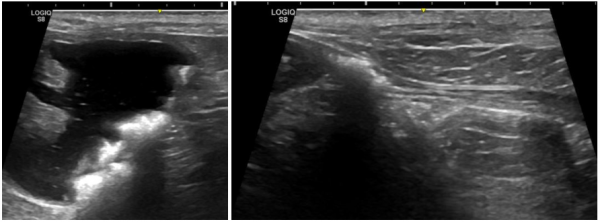

de70cef8385ff32e9ecfc65bf523daeb_1766384028_1273.png

└까미(까명) 방광결석 방사선

특히 복부 초음파방광결석의 위치·움직임·크기·요도 폐색 여부

가장 정확하게 파악할 수 있어 필수적인 과정입니다.

de70cef8385ff32e9ecfc65bf523daeb_1766384043_7167.png

┗까미(가명) 방광결석 초음파

까미는 방광, 요도, 신장에 결석이 있는 상태로 진단되었습니다.

다행히도 요도 결석이 요도 완전폐색을 유발하지 않은 상태라

응급 수술을 요하지는 않았습니다.